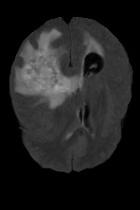

Current unsupervised anomaly localization approaches rely on generative models to learn the distribution of normal images, which is later used to identify potential anomalous regions derived from errors on the reconstructed images. However, a main limitation of nearly all prior literature is the need of employing anomalous images to set a class-specific threshold to locate the anomalies. This limits their usability in realistic scenarios, where only normal data is typically accessible. Despite this major drawback, only a handful of works have addressed this limitation, by integrating supervision on attention maps during training. In this work, we propose a novel formulation that does not require accessing images with abnormalities to define the threshold. Furthermore, and in contrast to very recent work, the proposed constraint is formulated in a more principled manner, leveraging well-known knowledge in constrained optimization. In particular, the equality constraint on the attention maps in prior work is replaced by an inequality constraint, which allows more flexibility. In addition, to address the limitations of penalty-based functions we employ an extension of the popular log-barrier methods to handle the constraint. Comprehensive experiments on the popular BRATS'19 dataset demonstrate that the proposed approach substantially outperforms relevant literature, establishing new state-of-the-art results for unsupervised lesion segmentation.